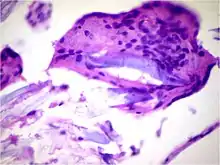

![]() | Diffuse B-cell lymphoma | Lymph node FNA specimen showing diffuse large B cell lymphoma. | Category: Histopathology of diffuse large B cell lymphoma | Diffuse large B-cell lymphoma |